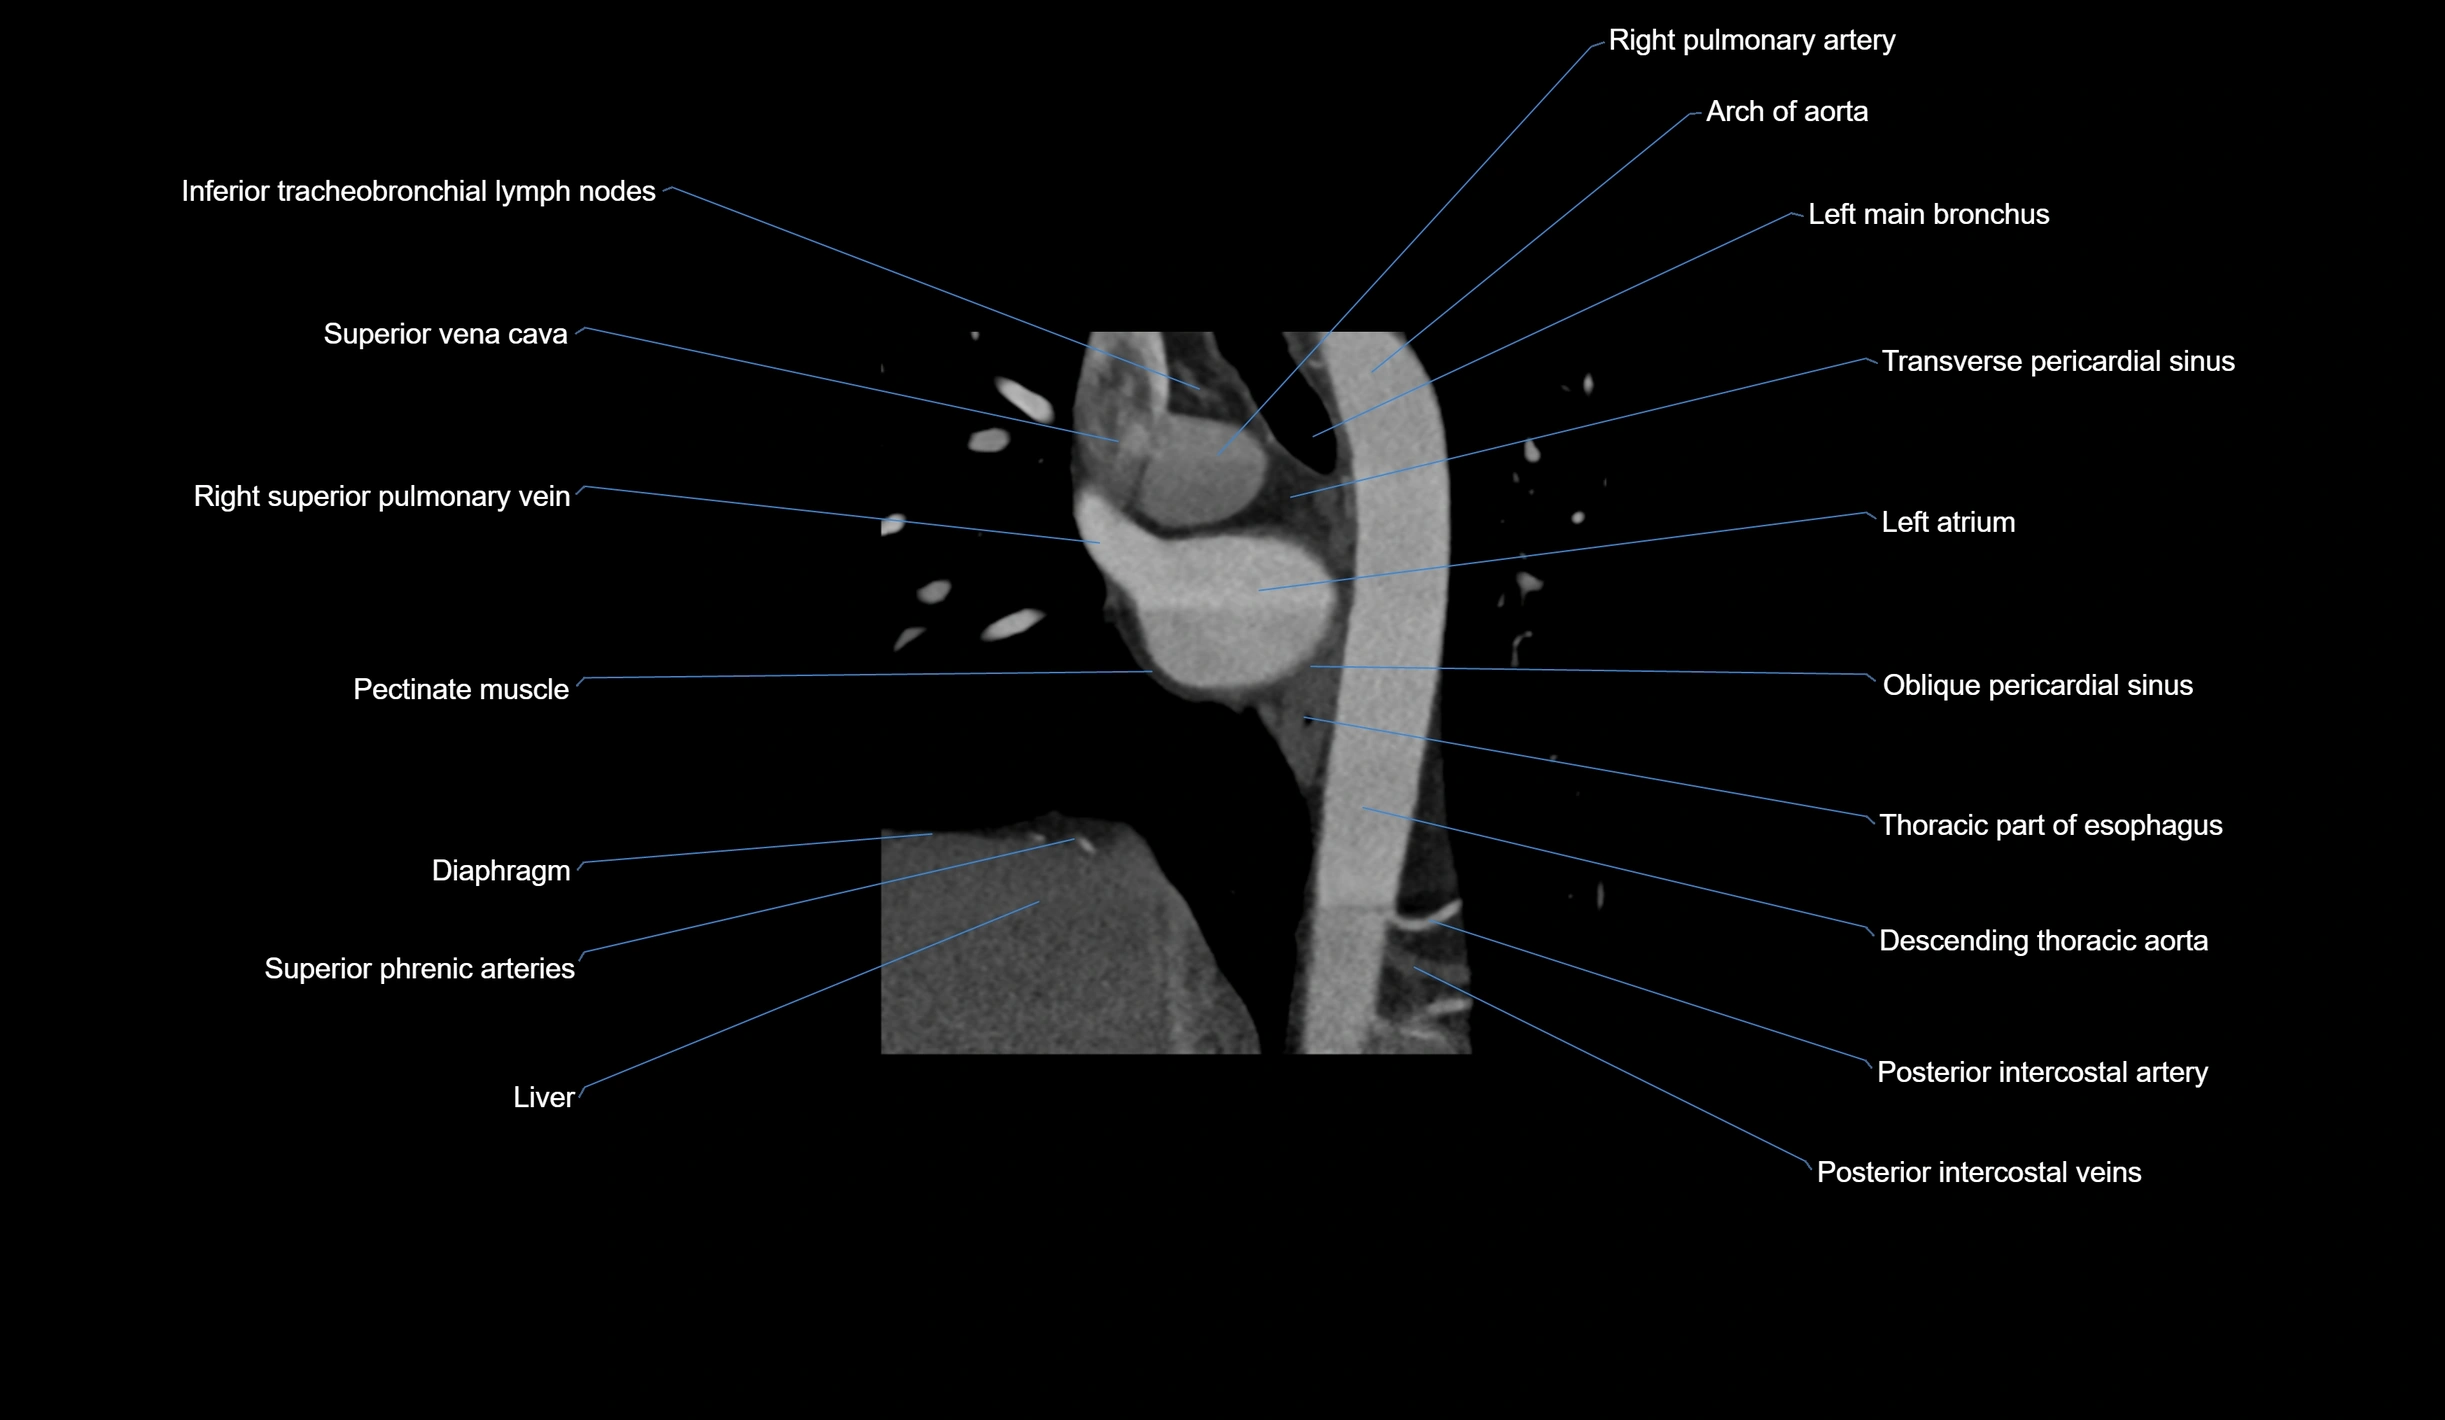

- Arch of aorta

- Azygos vein

- Inferior tracheobronchial lymph nodes

- Left main bronchus

- Oblique pericardial sinus

- Oblique vein of left atrium

- Posterior intercostal arteries

- Posterior intercostal veins

- Pulmonary trunk

- Right pulmonary artery

- Right superior pulmonary vein

- Sinus of venae cavae (sinus venarum)

- Superior vena cava

- Transverse pericardial sinus